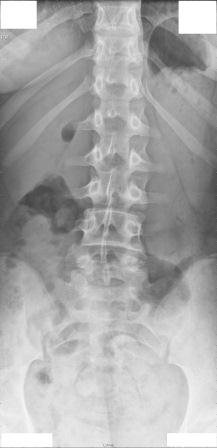

Hier sind alle Röntgenbilder.

Ist es jetzt anhand diesen Bildern nötig, zu einem Osteopathen zu gehen oder nicht?

- rückenansicht 1.jpg (11.74 KiB) 7115 mal betrachtet

Es ist in jedem Fall erforderlich !

Gerade bei einer 13-jährigen !

Ein Hohlkreuz ist zu sehen, der Rundrücken ist aufgrund der fehlenden Seitenansicht 3 nicht richtig einzuschätzen.

Die Skoliose im LWS Bereich (ich kann den Grad nicht abschätzen, oberer Bereich fehlt) sollte auf jeden Fall angegangen werden.

Ich habe den COB Winkel Lumbal ausgemessen, allerdings nur auf dem Bildschirm und komme auf ca 9° Lumbal. Eine deutliche Rotation erkenne ich nicht.

Auf dem frontalen RTG Bild ist zu sehen, dass das Becken nicht ganz gerade ist. Somit ist es möglich, dass Linkes Bein etwas kürzer ist als das Rechte und somit eine Statische Skoliose vorliegt, da die Statische Skoliose in Richtung des Verkürzten Beines geht und das ist auch hier der fall, die Verkrümmung Lumbal geht nach links.

Es währe sicher sinnvoll deine Schwester einem Orthopäden vorzustellen und bei der nächsten RTG Kontrolle, falls nötig die Beinlänge Ausgleichen.